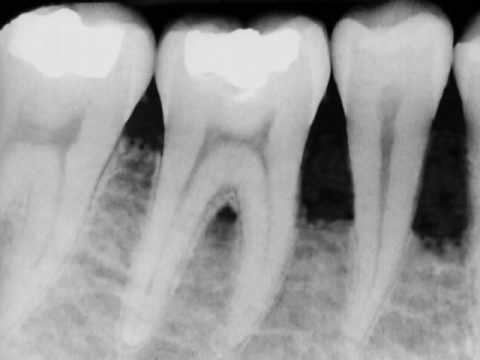

home Aesthetics Dental Bone Loss – Bone Grafting in Denville, NJ Dental Bone Loss – Bone Grafting in Denville, NJ By dentists Posted in Aesthetics Posted on May 17, 2017